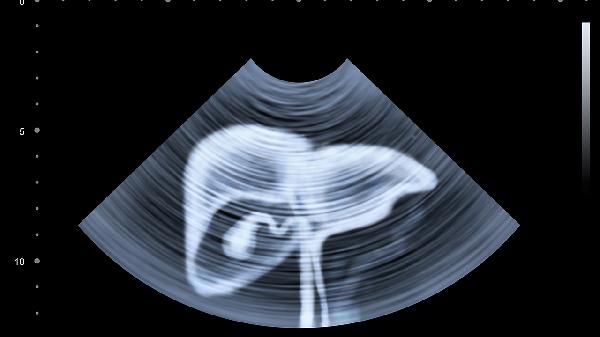

对于直径小于10毫米的孤立性胆固醇息肉,可采用体外震波碎石治疗。通过聚焦超声波粉碎胆固醇结晶,配合口服胆汁酸药物促进碎片排出。该治疗创伤小但存在复发可能,术后需每半年复查胆囊超声。